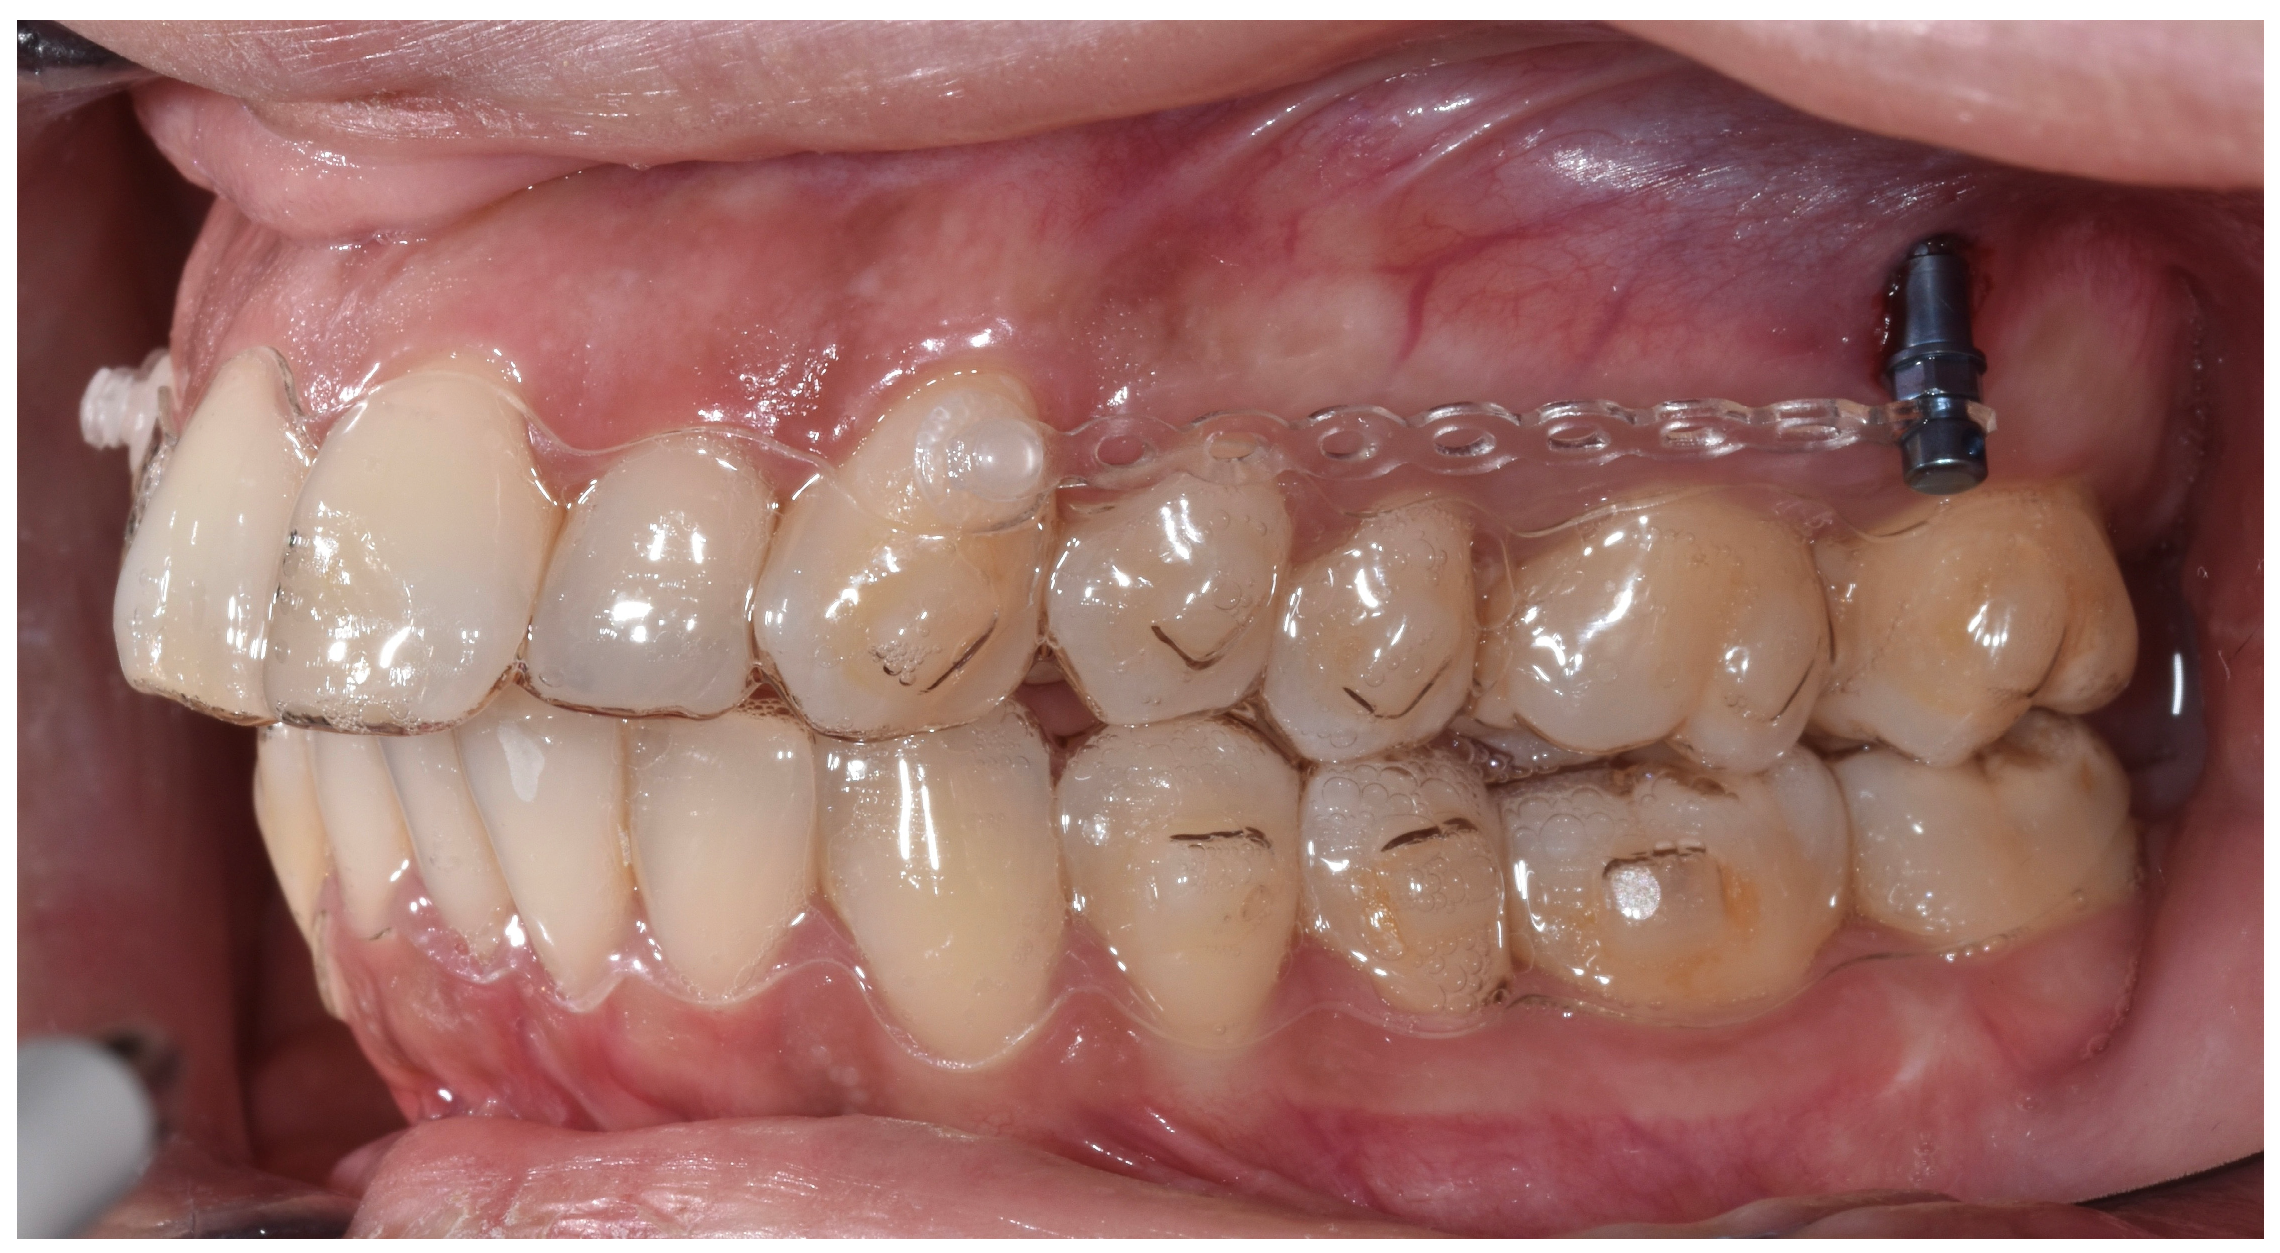

- Staderini, E.; Ventura, V.; Meuli, S.; Maltagliati, L.Á.; Gallenzi, P. Analysis of the Changes in Occlusal Plane Inclination in a Class II Deep Bite “Teen” Patient Treated with Clear Aligners: A Case Report. Int. J. Environ. Res. Public Health 2022, 19, 651. [Google Scholar] [CrossRef] [PubMed]

- Lu, W.; Li, Y.; Mei, L.; Li, Y. Preformed Intrusion Bulbs on Clear Aligners Facilitate Active Vertical Control in a Hyperdivergent Skeletal Class II Case with Extraction: A Case Report with 4-Year Follow-Up. APOS-Trends Orthod. 2023, 13, 46–54. [Google Scholar] [CrossRef]